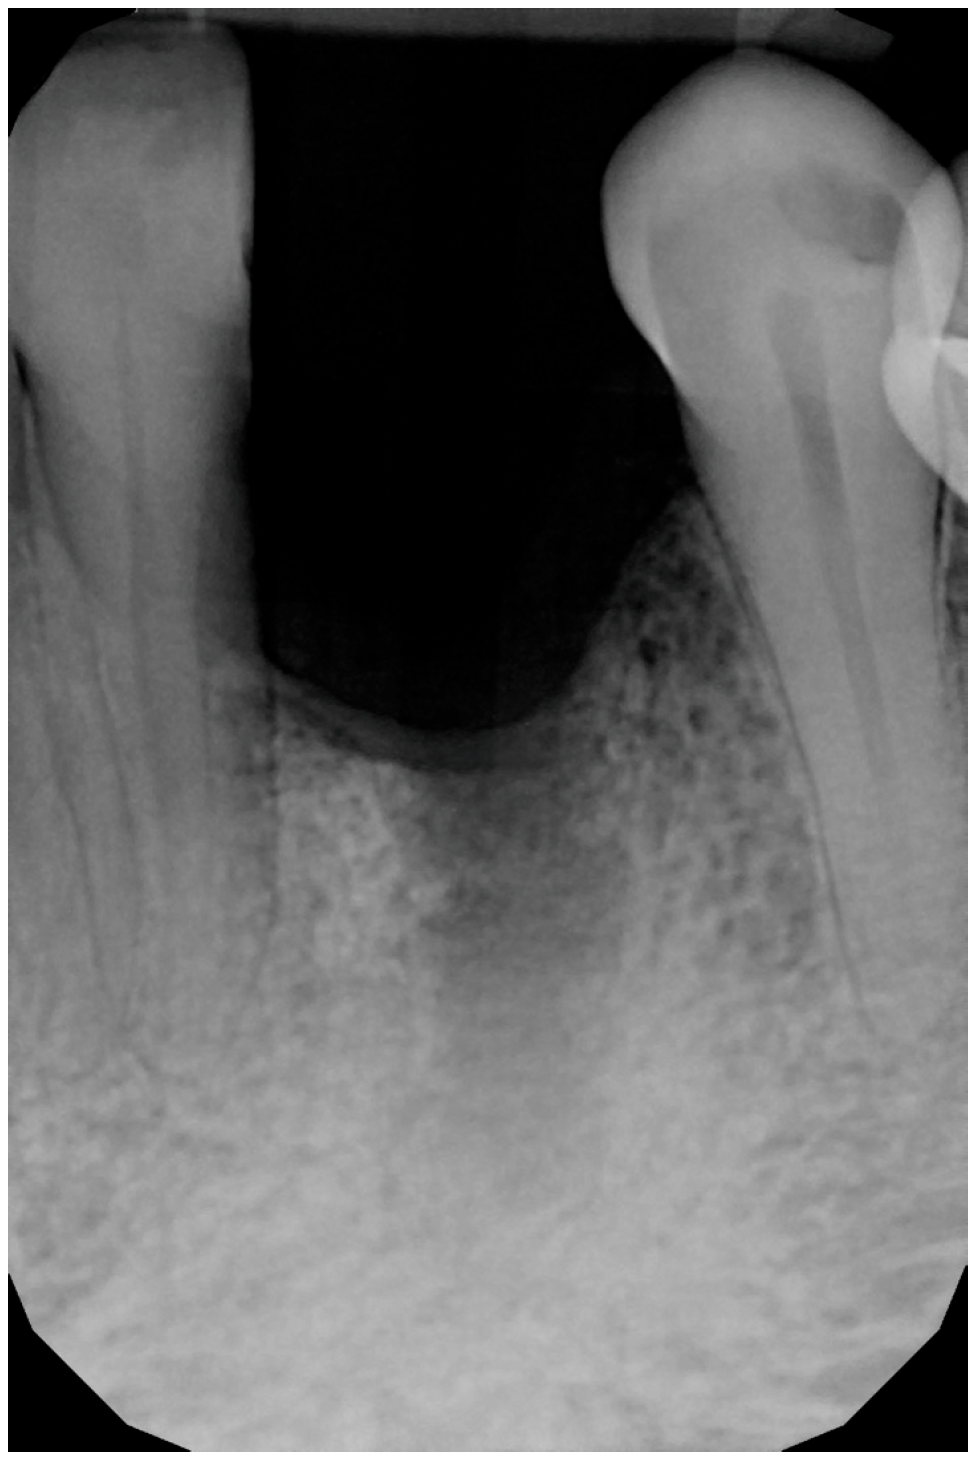

A 56-year-old male patient has been under our care for several years. The canine tooth in position 33 was treated 10 years ago using guided tissue regeneration (GTR) to address an infrabony defect. At that time, the biomaterial employed was an anorganic bovine bone-derived matrix (ABBM) in conjunction with a resorbable membrane. After 7 years, the tooth began to exhibit signs of internal root resorption and ultimately fractured (Figure 1).

Figure 1. Intraoral X-ray at baseline, highlighting the damaged root of element 33.

Figure 2. Intraoral radiograph following the extraction of the canine.